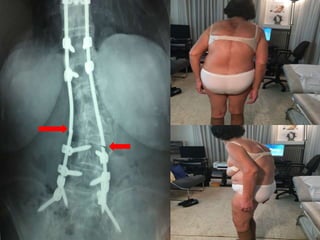

Top-off

Οστεοπώρωση

Π.Μ.

F 80

28-7-06

F 82

30-8-08

Loss of stabilization

Top – off phenomenon

above

bellow

T-Score: 3.5